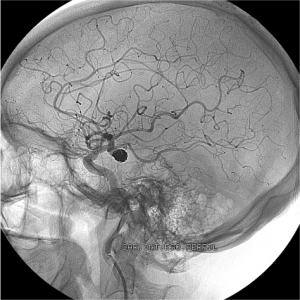

The procedure should be done within six hours after the stroke starts, and in most cases after the patient receives tPA, according to the guidelines. To remove the clot, doctors thread a catheter through an artery in the groin up to the blocked artery in the brain. The stent retriever opens and grabs the clot, allowing doctors to remove the stent with the trapped clot.